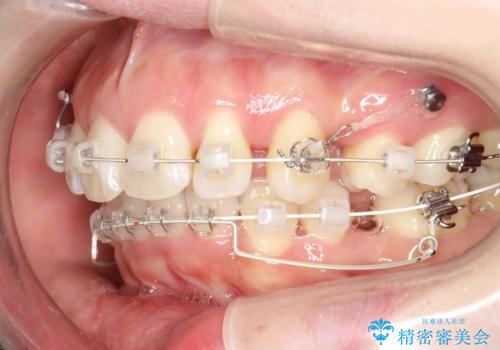

抜歯をして前歯を下げ、ガタつきを取り除く ワイヤー矯正

- 矯正装置

- 審美装置

- 上顎両側第1小臼歯、下顎左側第2小臼歯の3本を抜歯、ラビアルのワイヤー矯正を計画した。